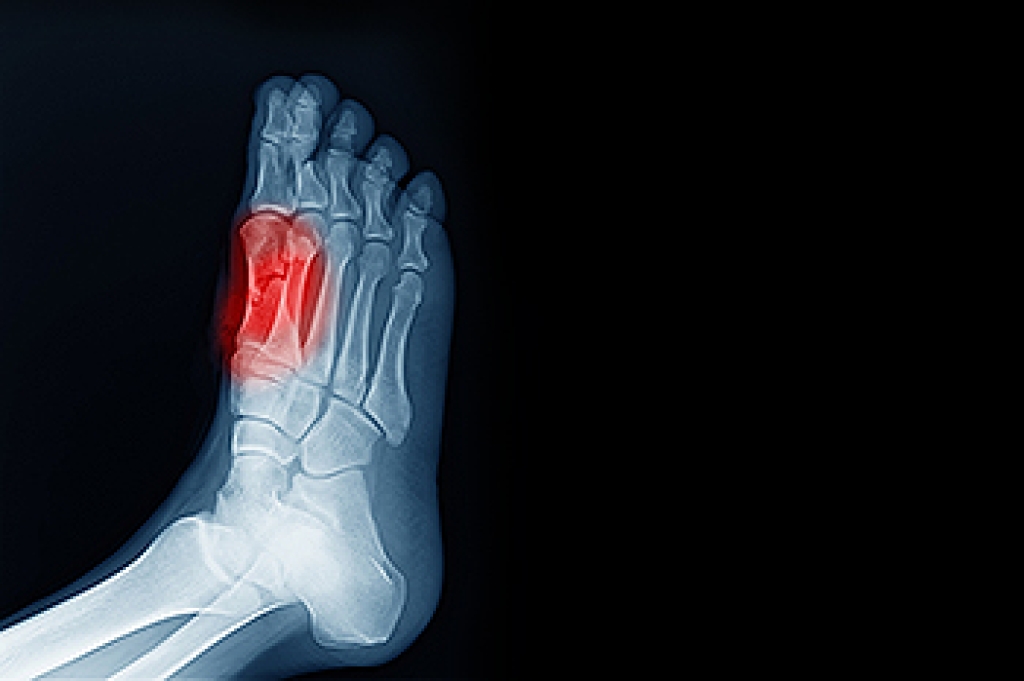

Sesamoiditis affects the small sesamoid bones located beneath the big toe joint near the ball of the foot. It occurs when these bones become inflamed, often due to repetitive pressure or overuse, making it a common concern for runners and athletes who place repeated stress on the forefoot. Symptoms include pain under the big toe, swelling, tenderness when walking or running, and difficulty bearing weight on the affected foot. Causes can include high-impact activities, wearing improper footwear, flat feet, or increased training intensity. A podiatrist can evaluate the foot, provide custom orthotics, recommend activity modifications, and implement therapies such as padding, taping, or targeted exercises to reduce stress on the sesamoid bones. If you have pain in this part of your foot, it is suggested you consult a podiatrist who can accurately diagnose and treat what may be going on.

Sesamoiditis is a condition of the foot that affects the ball of the foot. It is more common in younger people than it is in older people. It can also occur with people who have begun a new exercise program, since their bodies are adjusting to the new physical regimen. Pain may also be caused by the inflammation of tendons surrounding the bones. It is important to seek treatment in its early stages because if you ignore the pain, this condition can lead to more serious problems such as severe irritation and bone fractures.